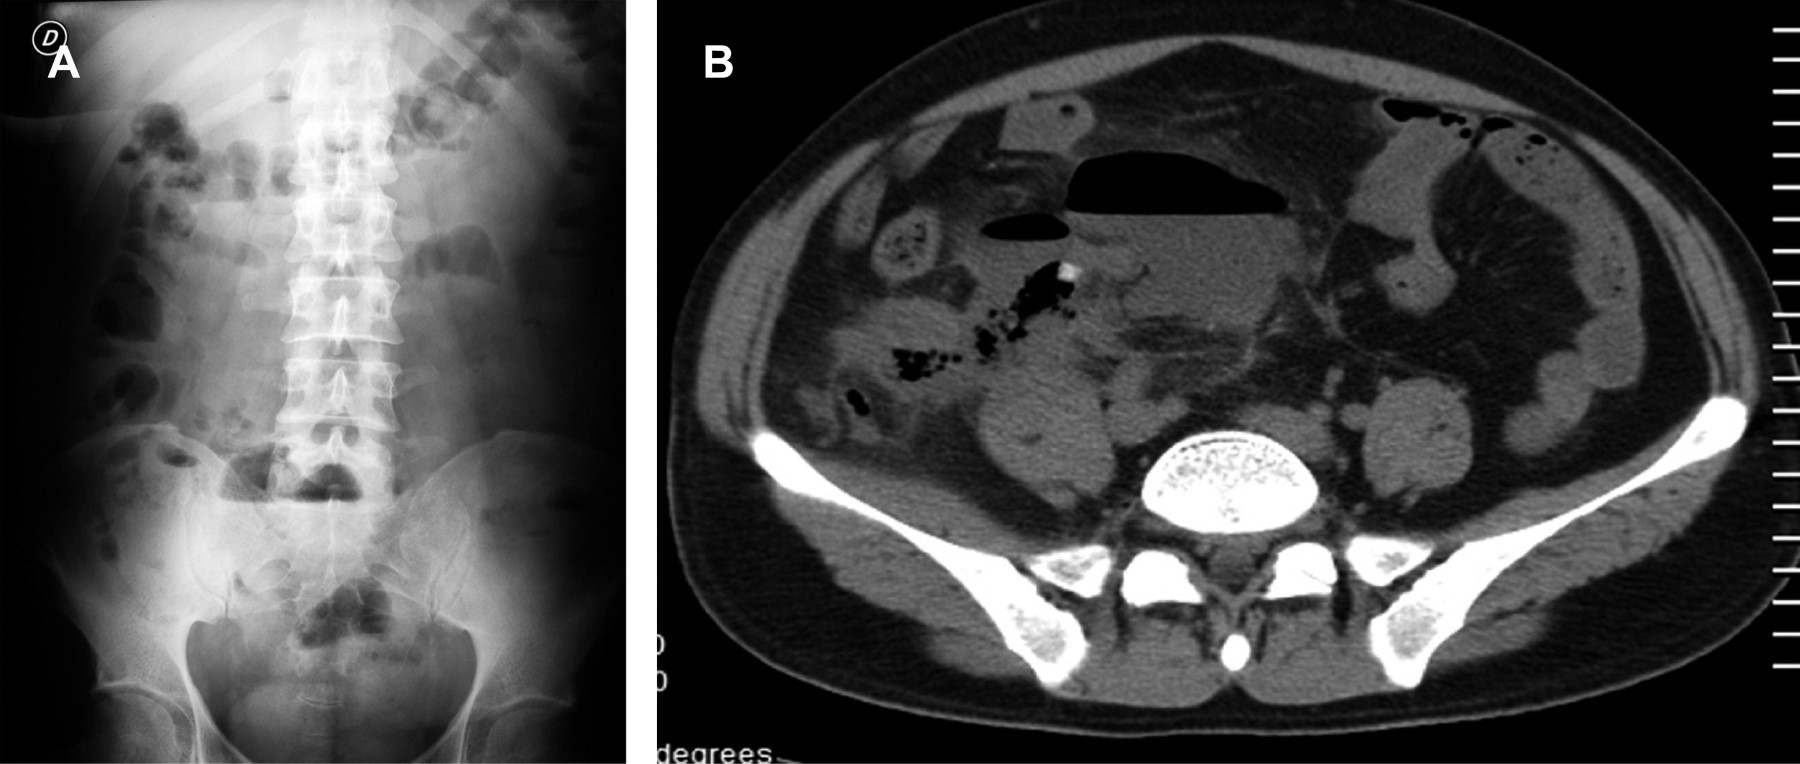

APARIENCIA POR TOMOGRAFíA COMPUTARIZADA (TC) DEL AIA (Figuras 2 y 3)

La TC abdominopélvica para la búsqueda del AIA postoperatorio es diagnóstica en una proporción importante de casos en la primera semana, la mayoría de los cuales son manejados por drenaje percutáneo o quirúrgico; sin embargo, se debe realizar el estudio sin importar el tiempo que haya pasado del evento quirúrgico si la clínica así lo indica.3

La TC abdominopélvica con contraste oral es la prueba de imagen de elección cuando se sospecha un absceso, permitiendo localizarlo entre asas y definir fístulas, mientras que el contraste intravascular (IV) se concentra en su pared, delimitando su localización, con un 10% de falsos positivos negativos.

Los AIA son colecciones localizadas de tejido inflamatorio purulento causado por una mezcla de bacterias incluyendo anaerobias y de la flora habitual, caracterizados por ser una colección necrótica central con leucocitos y tejido circundante que, por TC, se demuestra como una región de baja atenuación. Por fuera de ella, hay dilatación vascular, afección parenquimatosa y proliferación fibroblástica. Este tejido conectivo vascularizado aparece en TC como un anillo bien definido, reforzado generalmente posterior al contraste IV. El signo más específico del AIA en TC es la identificación de aire extraluminal dentro de una colección líquida resultante de la formación bacteriana de gas, observado en solo el 50%.

La TC es el método de elección para estudiar el retroperitoneo, con posibilidades de ofrecer una alternativa terapéutica no quirúrgica. La localización primaria de la colección más frecuente fue el espacio pararrenal anterior izquierdo y la corredera parietocólica izquierda en los casos de pancreatitis aguda. El absceso periapendicular o el flemón ocurren en el 2-7% de todos los pacientes con apendicitis aguda (Figura 2). La TC posee el potencial de identificar al área apendicular, facilita la identificación del flemón del absceso con licuefacción, define la extensión periapendicular hacia fondos de saco o bien retroperitoneal y permite la guía del drenaje del absceso periapendicular como alternativa del drenaje quirúrgico.

El AIA menor de 3 cm de diámetro se resuelve frecuentemente con manejo conservador y antibioticoterapia (Figuras 2 y 3).